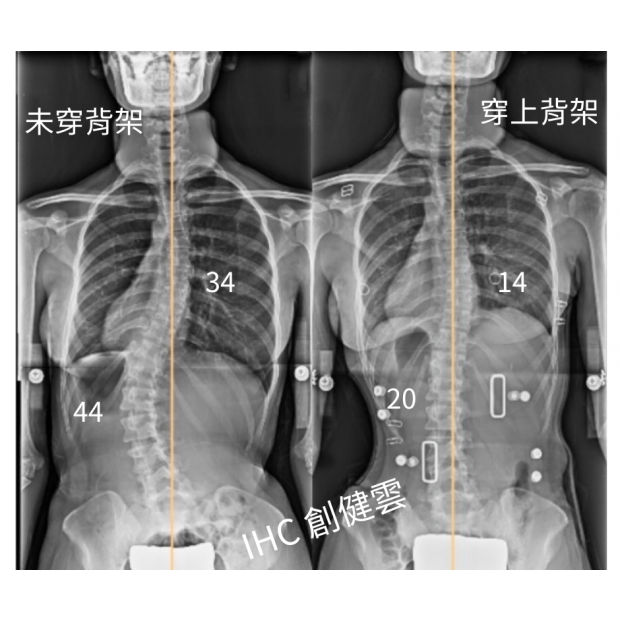

13歲女孩,胸彎31度腰彎44度

13歲女孩,胸彎31度腰彎44度 穿上背架後立即矯正效果